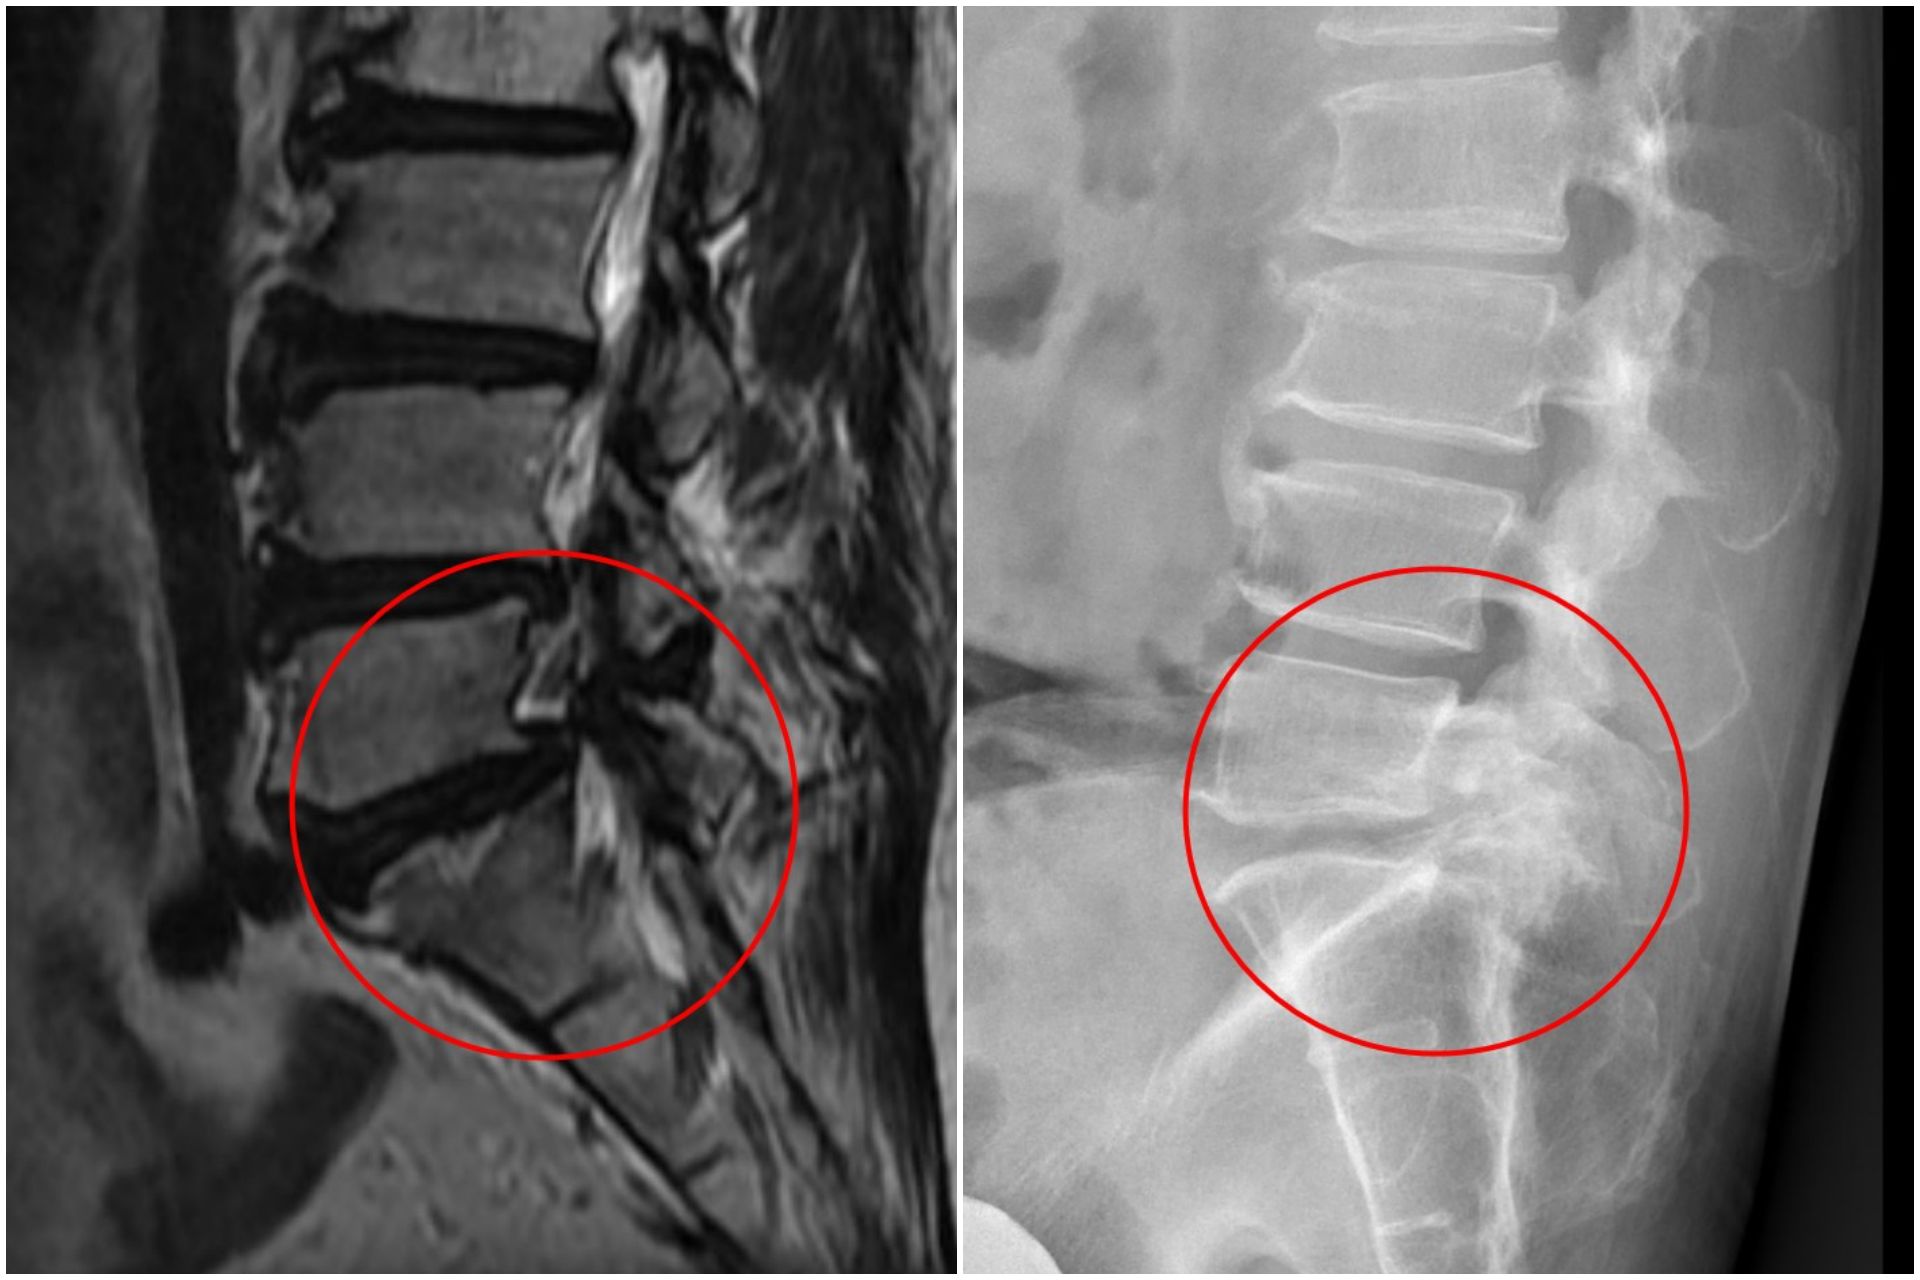

影像檢查顯示,張先生的第五節腰椎椎弓骨折合併脊椎解離。洪祥益主任表示,這類病人多半表現為腰痠背痛、久坐久站困難,通常可先藥物治療觀察,但相較於其他類似問題的病人,張先生疼痛異常明顯,手術中發現脊椎關節內長滿痛風石,這些痛風石如白色黏稠物般,附著在神經與關節縫隙間,若不清乾淨,就會持續引發神經發炎與疼痛,甚至比坐骨神經痛更強烈。團隊透過顯微鏡,在不傷及神經的情況下,仔細將痛風石刮除清理,再以微創固定融合手術完成治療。